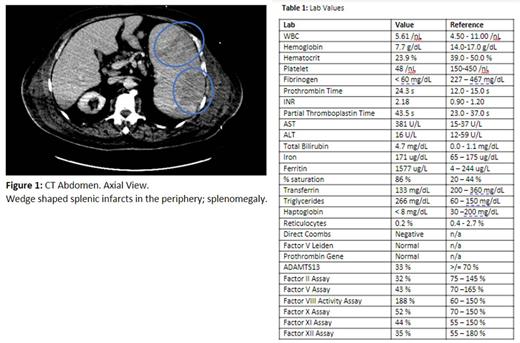

A 77-year-old male with history of deep vein thrombosis (DVT), Parkinson's disease, and lumbar radiculopathy on chronic prednisone, presented for progressive generalized weakness, leg pain, and confusion. Initial labs showed normocytic anemia, thrombocytopenia, low fibrinogen and elevated INR and liver enzymes (Table 1). Multiple ischemic signs were noted including acute on chronic DVT, as well as findings of marked splenomegaly with wedge infarcts and periportal lymphadenopathy on abdominal ultrasound and CT (Figure 1). The underlying etiology of these findings was unclear and broad differential work up was pursued. Given the anemia and thrombocytopenia on presentation, the patient received multiple blood products including platelets, red blood cells, fresh frozen plasma and cryoprecipitate, in addition to vitamin K. No schistocytes were seen peripherally, and DIC/TTP workup was negative. Multidisciplinary teams evaluated the risk versus benefit of anticoagulation with heparin drip considering evidence of multi-organ ischemic damage. It was briefly initiated, but later held due to persistent thrombocytopenia and abnormal liver function. Further work up only revealed hemolysis with a low haptoglobin and elevated LDH (Table 1). However, the follow up Coombs test was negative, ruling out immune mediated hemolysis. While symptomatic management continued, blood parasite screen obtained on admission indicated Babesia microti infection. Upon repeat testing, no evidence of babesia was identified on labs or blood smear. However, this finding was skewed by the multiple transfusions the patient received. Unfortunately, the clinical course rapidly declined, and the patient's family elected a transition to comfort care measures whereby the patient expired within two days of presentation. Remaining work up resulted posthumously, with CD25 levels elevated at 38,354.0 pg/mL. Coupled with the previously established splenomegaly, pancytopenia, hypertriglyceridemia, and elevated ferritin, these findings indicate a diagnosis of HLH, likely triggered by Babesia microti infection.